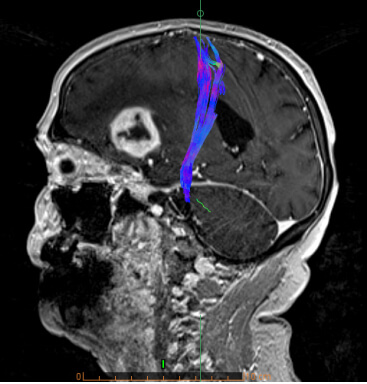

- Τractography